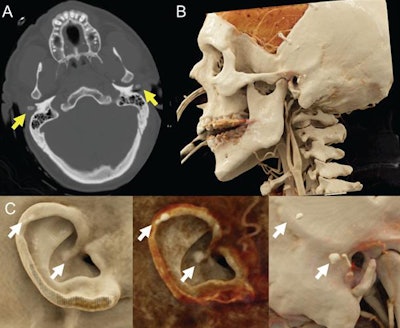

In a recent case study, Caton and Malone acquired the CT scans of a 47-year-old man with a history of traumatic brain injury who had previously undergone craniectomy to relieve pressure in the skull. They used advanced volume rendering software (syngo.via, Siemens Healthineers) to cinematically render the CT data and generate photorealistic images.

The resulting cinematically rendered images greatly improved depth perception as well as the visualization of surface textures and underlying calcification below the surface of the skin, compared with conventional CT, Caton told AuntMinnie.com. As a result, the researchers were able to spot calcification in both of the patient's ears, which physicians had not recognized on a prior physical exam.

Manually adjusting the CT window and level settings also gave the researchers the opportunity to selectively emphasize or suppress tissues with different radiographic densities on the cinematically rendered images -- enabling them to alternate between views of the skin's surface and the underlying bony and soft-tissue structures.